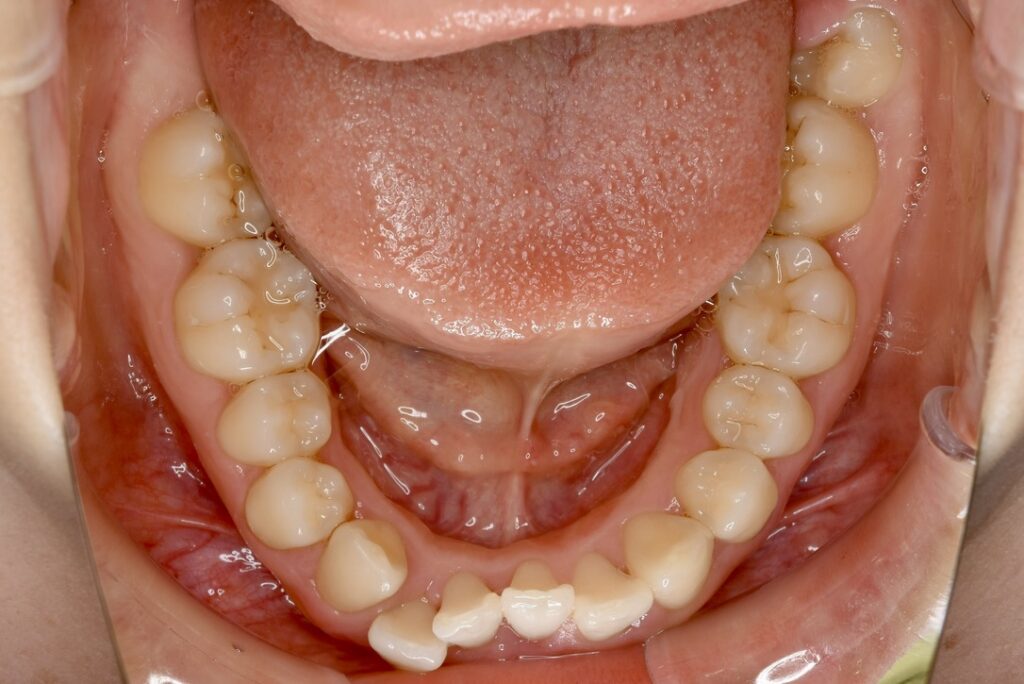

21歳 女性 治療期間:1年1ヶ月

叢生(ガタガタ)

マウスピース矯正装置(インビザライン)

BEFORE

AFTER

主訴

周りの人の歯並びが綺麗で自分の歯並びを治したくなってきた。

診断名・主な症状

叢生

治療内容

上下とも歯並びの横幅を広げながら、でこぼこを解消しました。

マウスピース矯正(インビザライン)

抜歯あり(智歯抜歯)

治療期間

1年1ヶ月

通院回数

10回

費用

85万円程度(税別)

リスク・副作用

痛み、歯肉退縮、歯根吸収、抜歯に伴う出血や腫れが生じることがあります。